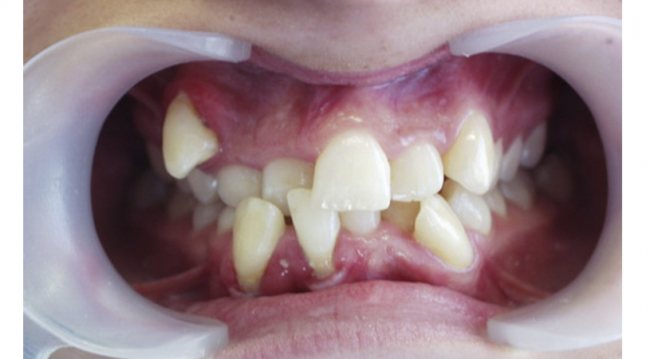

Это самые тяжелые и серьезные отклонения. При такой аномалии, зубы обычно занимают неправильное положение, причем происходит это не только вне зубного ряда, но и внутри него. Различают сразу несколько видов неправильного положения зубов:

- Дистальное положение. В этом случае зуб сильно смещается назад из зубного ряда.

- Мезиальное положение. В этом случае зубы, наоборот, сильно выпадают вперед.

- Вестибулярное положение. Так говорят в том случае, когда зубы располагаются близко к губам или щекам, в зависимости от их вида.

- Оральное положение. В данном случае практически все зубы сильно смещаются вглубь полости рта.

- Супраположение. Здесь зубы могут быть расположены аномально выше окклюзионной кривой, а также значительно ниже нее, но в этом случае аномалия получит название – инфраположение.

- Тортоаномалия. Один или несколько зубов могут быть развернуты вдоль вертикальной оси. Если некоторые зубы меняются местами, то это называется транспозицией.

Устранить все эти аномалии может врач-ортодонт. Сделать это не так сложно. Современные брекет-системы и ортодонтические аппараты творят настоящие чудеса за короткое время.